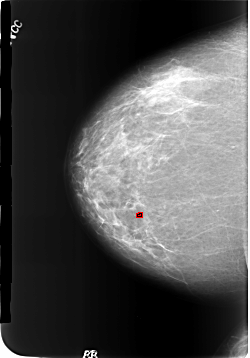

FILE: B_3186_1.RIGHT_CC.OVERLAY

TOTAL_ABNORMALITIES 1

ABNORMALITY 1

LESION_TYPE CALCIFICATION TYPE LUCENT_CENTERED DISTRIBUTION N/A

ASSESSMENT 2

SUBTLETY 4

PATHOLOGY BENIGN

TOTAL_OUTLINES 1

BOUNDARY